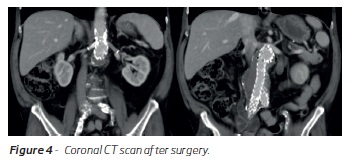

Before discharge, the patient had a control CT scan where no evidence of endoleaks were detected. (Figure 3,4 and 5)